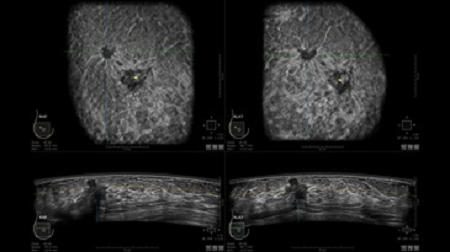

GE INVENIA ABUS – это современный УЗИ аппарат, который создан для точной и эффективной диагностики сканирования с высокой плотностью молочных желез. Выявляемость патологий раковых и предраковых стадий заболевания составляет 55%, что в конечном счете позволяет ставить врачу точные и своевременные диагнозы. Традиционные методы использования маммографии не показывают такой выявляемости, ограничиваясь лишь 3-38%.

УЗИ-аппарат GE INVENIA ABUS позволяет проводить максимально операторонезависимые процедуры, что значительно снижает риск неправильной постановки диагноза и сопутствующие издержки на обработку информации. Система готовит отчет в течение 3-х минут после сканирования, это безусловное преимущество по сравнению с обычным УЗИ сканером.

• Получение объемных 3D изображений с возможностью покадрового просмотра

• Алгоритмы обработки изображений: алгоритм однородности изображения ткани (TEA), подавление зернистости, компенсация акустической тени от соска (NSC), определение границ молочной железы (BBD), определение стенки грудной клетки

• Отображение объемных 3D ультразвуковых изображений, которые состоят из традиционных поперечных и воссозданных коронарных и сагиттальных проекций

• Многооконный просмотр: 4 - 12 изображений

• Стандартизованная ориентация изображения: «толстый срез» в коронарной плоскости; поперечная; сагиттальная плоскость; радиальный и антирадиальный поворот изображения; просмотр исключительно области интереса

• Одновременный просмотр двух изображений для сопоставления в коронарной плоскости